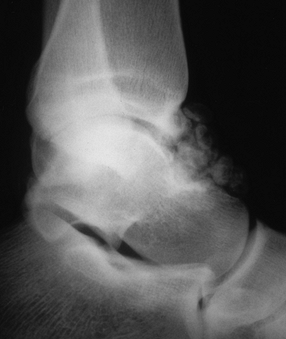

lengths and insert the appropriate size screws (Fig. 93.22A, Fig. 93.22B and Fig. 93.22C).![]() Figure 93.22. Arthroscopically assisted treatment of a medial malleolar fracture. A: Preoperative x-ray study shows a displaced fracture with rotation. B: Figure 93.22. Arthroscopically assisted treatment of a medial malleolar fracture. A: Preoperative x-ray study shows a displaced fracture with rotation. B:

Intraoperative fluoroscopy shows initial fracture reduction and pin

placement. These guide pins can be used to complete the reduction and

then cross the fracture for screw placement. C: Screw placement and fracture healing 8 weeks postoperative.